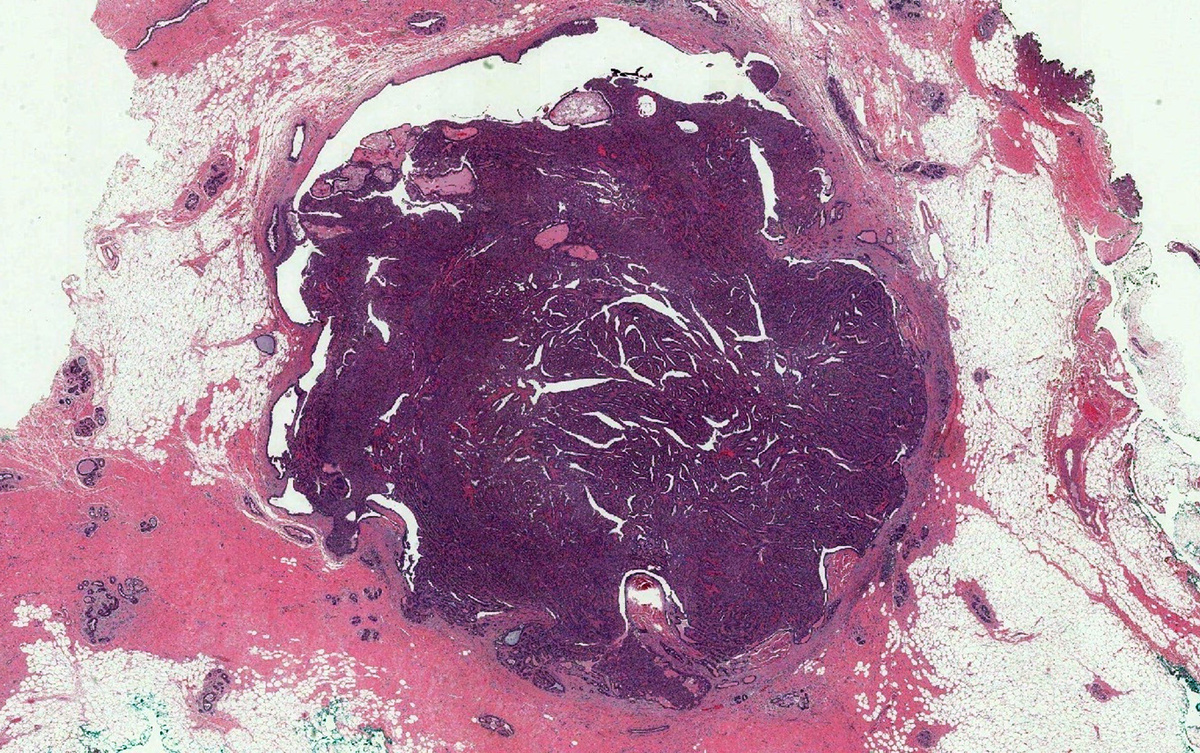

Внутрипротоковая папиллома молочной железы.

Внутрипротоковая папиллома - это доброкачественная опухоль, обнаруживаемая в протоках молочной железы.

Одиночная внутрипротоковая папиллома чаще всего располагается в центральном протоке кзади от соска. Множественные внутрипротоковые папилломы могут располагаются в любом секторе молочной железы, поражая периферические протоки.